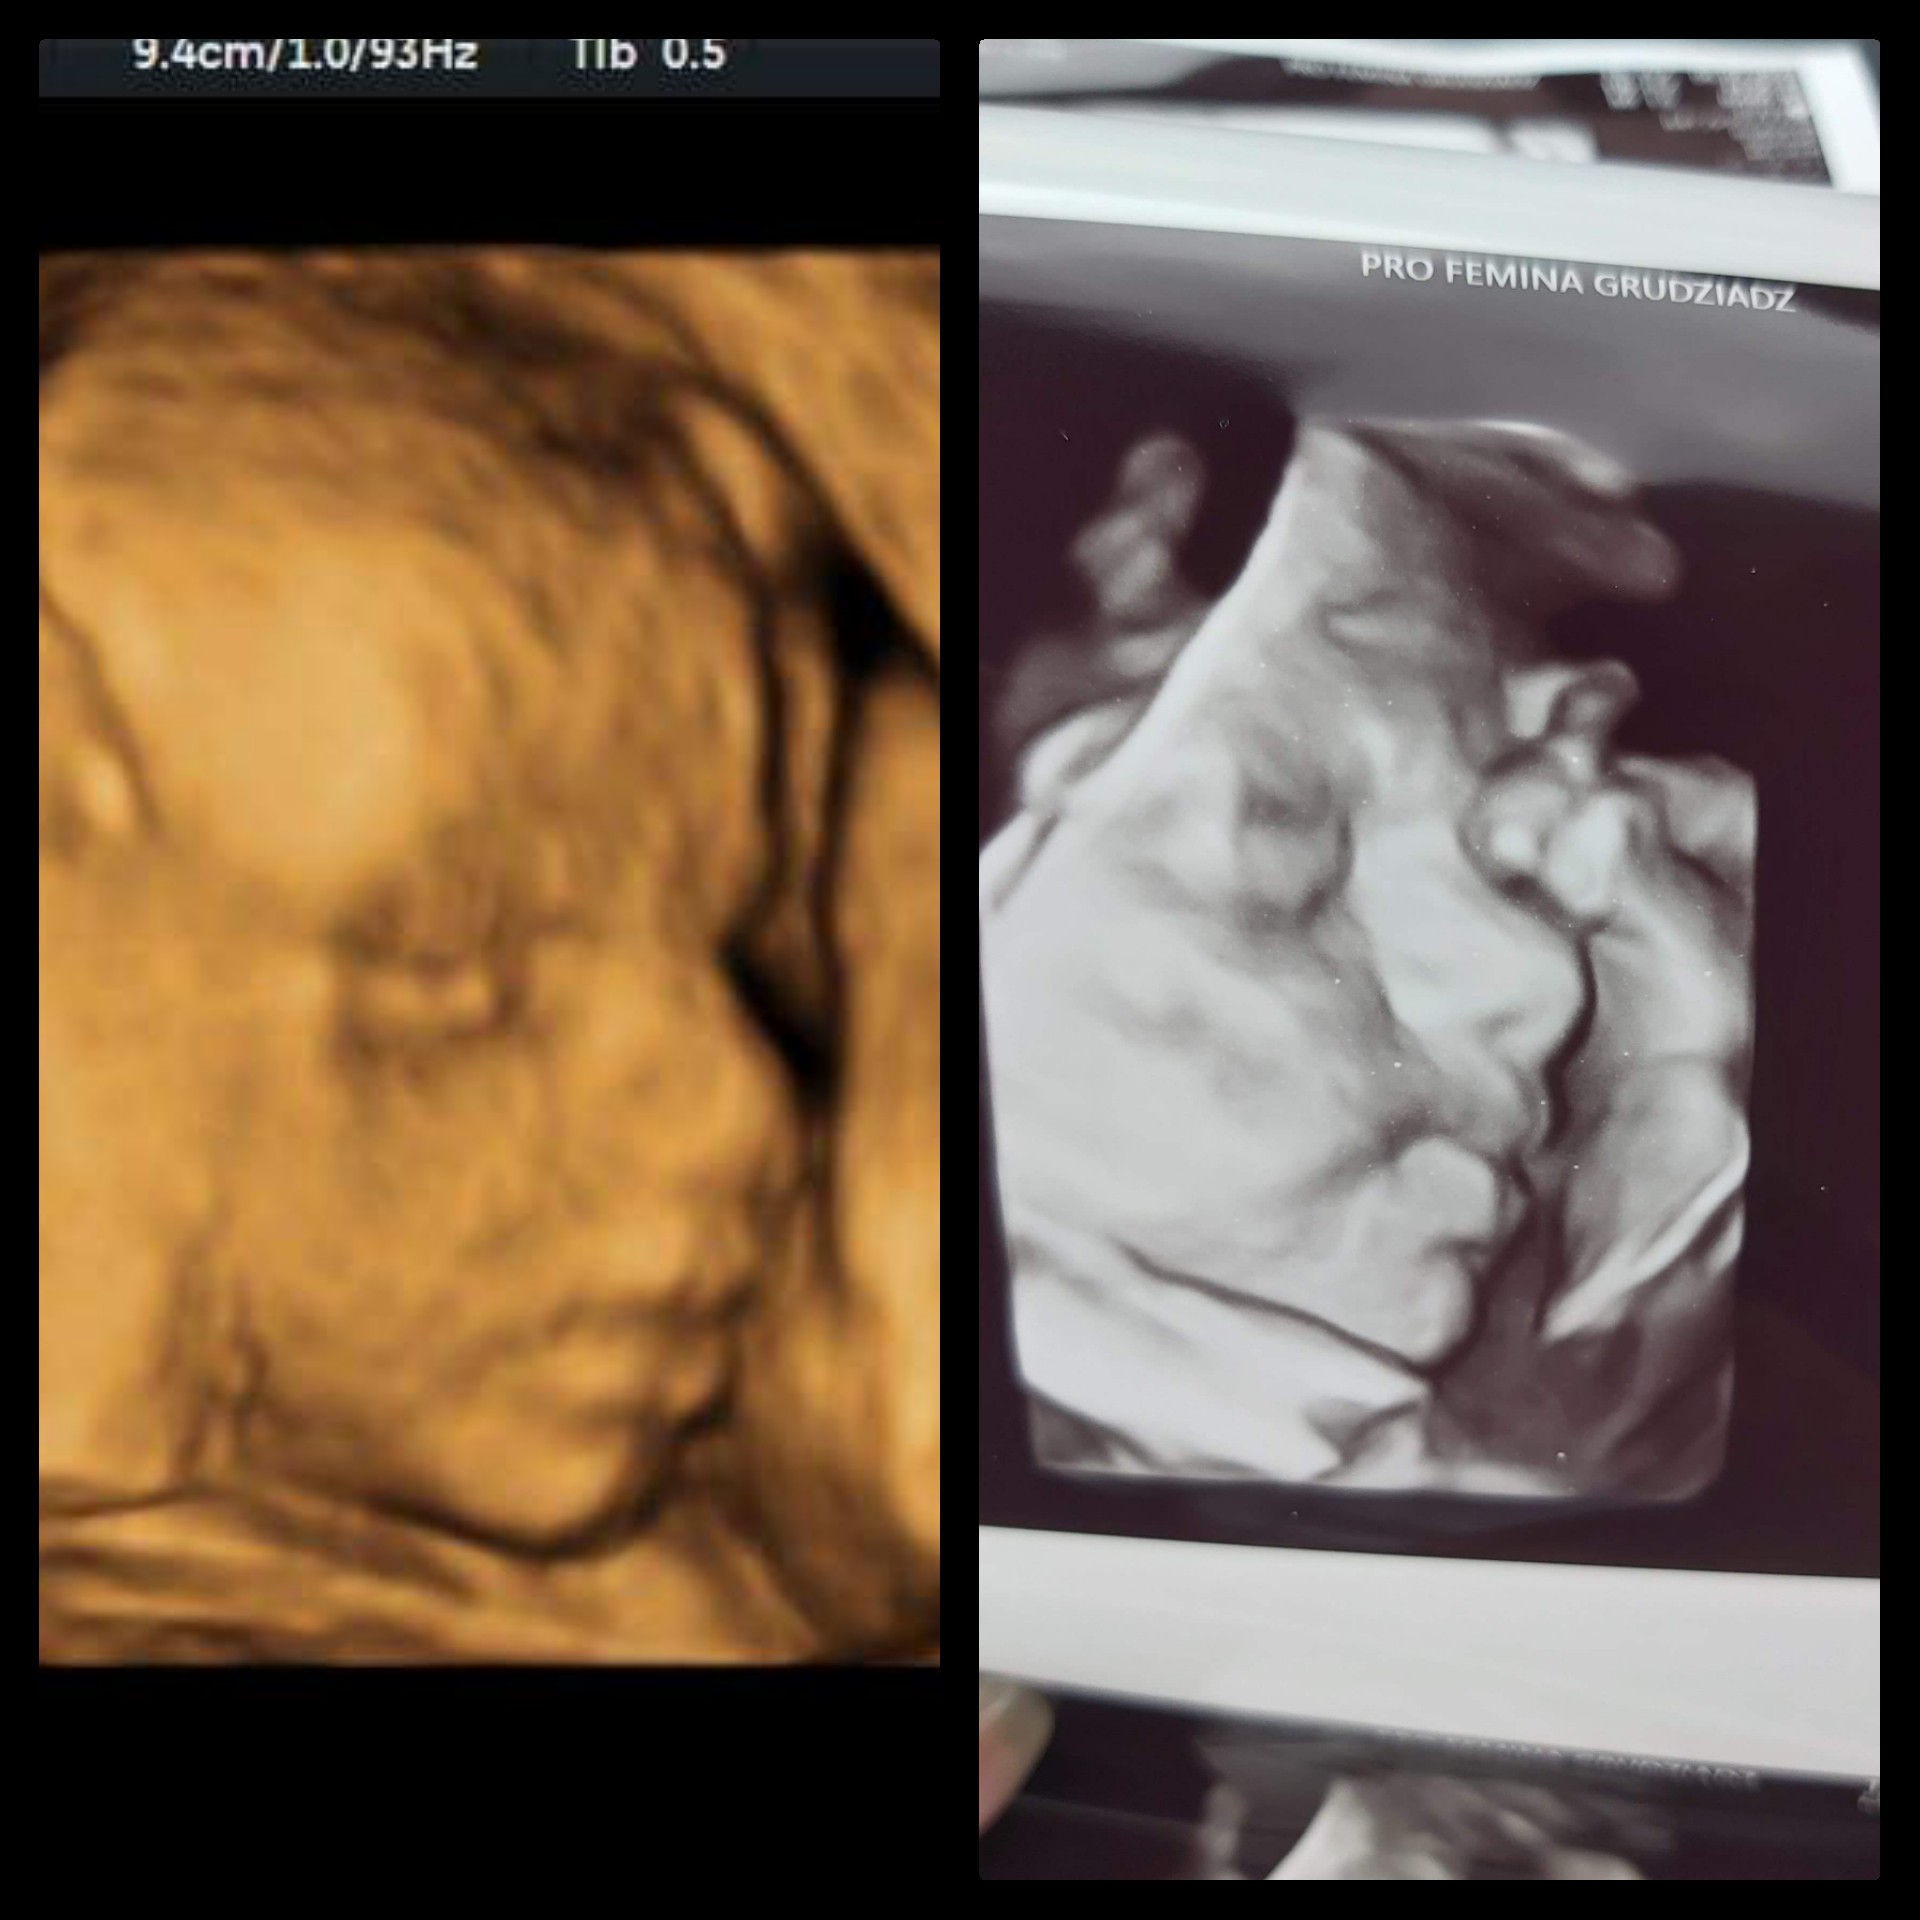

Witajcie dziewczynki ! Ja na wizytę idę we wtorek

już się doczekać nie mogę jaki ten mój chłopczyk już duży